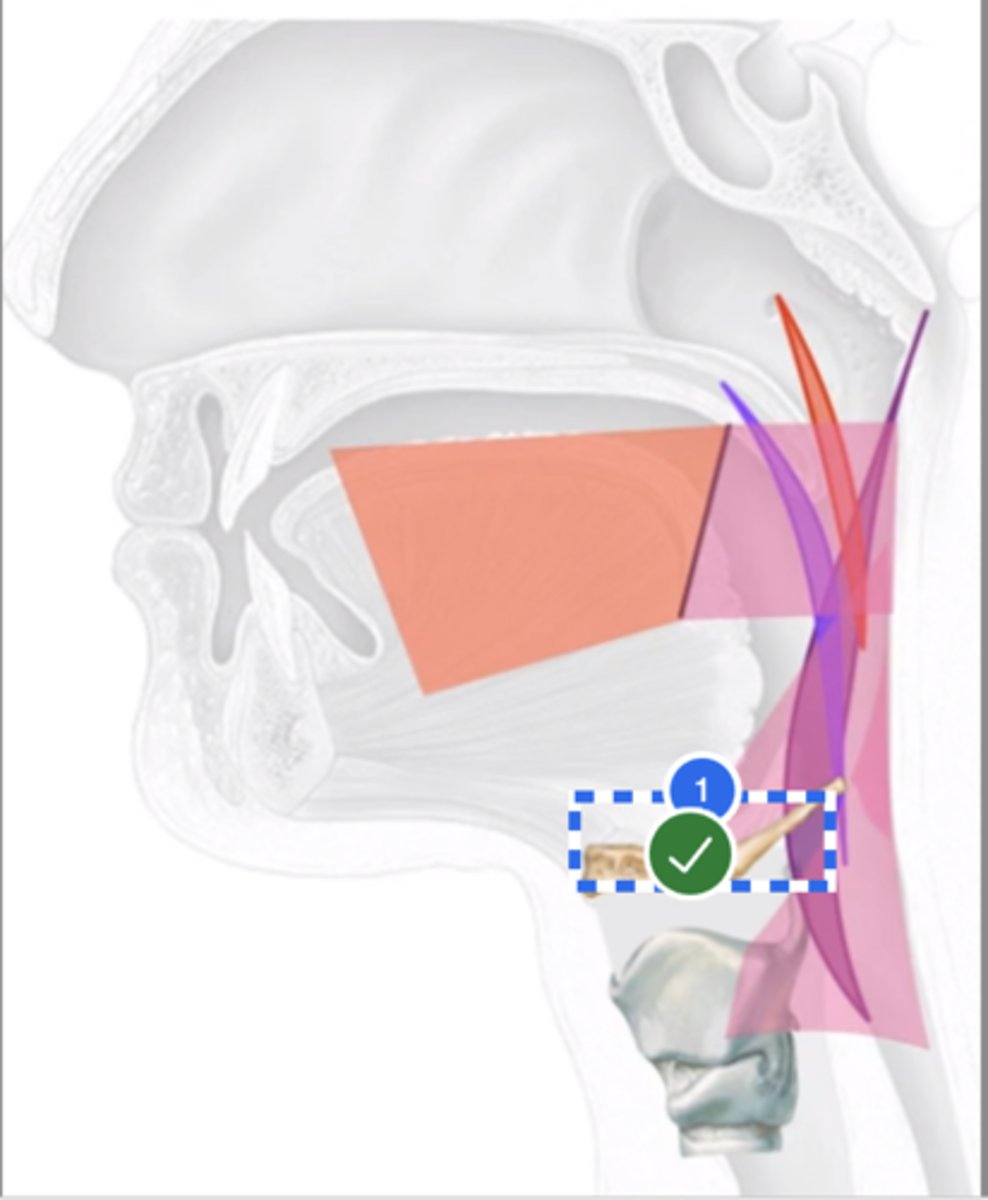

Label Nasopharynx (lateral view)

Label Nasal cavity (lateral view)

Label oropharynx (lateral view)

Label hypopharynx/ hylolarynx

Label tongue (lateral view)

Label soft velum/ palate (lateral view)

Label hard palate (lateral view)

Label mandible (lateral view)

Label base of tongue (lateral view)

label hyoid bone (lateral view)

Label epiglottis (lateral view)

label Line of true vocal folds (lateral view)

label Thyroid cartilage (anteriorly) (lateral view)

Label posterior cricoid (lateral view)

Label esophagus (lateral view)